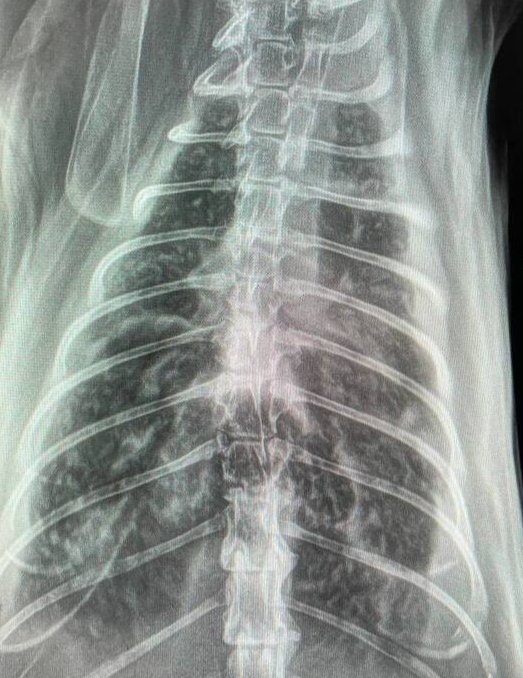

Дано: возрастная кошка с длительным ринитом.

Пришли на прием 13.10 с формулировкой «гноится глазик». Я увидел их 14.10 и всё же уговорил пойти на кт, а там абсцесс за левым глазом, фронтит (забиты и лобные пазухи, и носовые ходы).

После проводим фронтотомию - по сути, бурим дырку в лобную пазуху для промывания и вымывания всего скопившегося гноя.

Промыв всё большим количеством тёплого стерильного физ.раствора, зашиваем всё. Плюсом удаляем назофарингеальный полип.